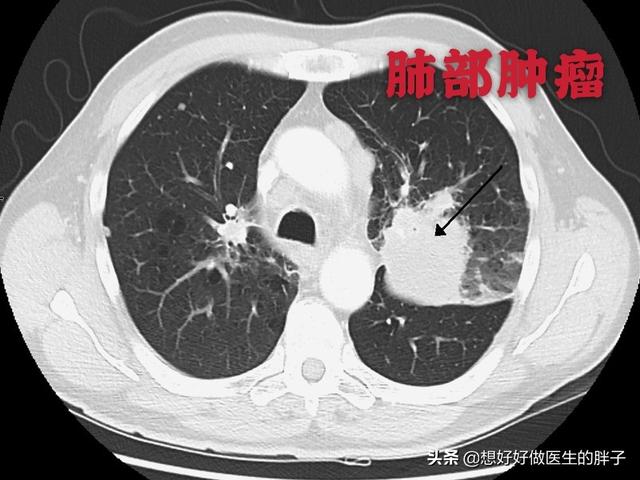

左肺にあるこの不規則な結節が原発巣で、わずか2.6cmしかない。このような骨転移を伴う肺がんは、もはや手術不可能です。肺がんはあまりにもありふれた病気であり、初期症状の中には非典型的なものや無症状のものさえあるからだ。肺がんの約30%では、転移の症状が最初の症状であり、さらなる肺がんが発見される前に転移が最初に発見される。

数日前、肺がんの骨転移の患者を診断したばかりで、彼の症状は長期的な腰背部痛で、彼らはいつも腰椎の筋肉の緊張、または腰椎椎間板ヘルニアに苦しんでいると思ったが、気にしなかった、本当に痛みが深刻で、下肢の神経症状が現れ、唯一の検査のために病院へ、そのCT検査に与えられた、明らかな椎骨破壊があることがわかった。......病歴を詳しく調べると、患者は長期的に咳の症状があるため、肺がんの骨転移が強く疑われ、肺のCT検査を行ったところ、主な焦点は......巨大な肺がんであることがわかった。